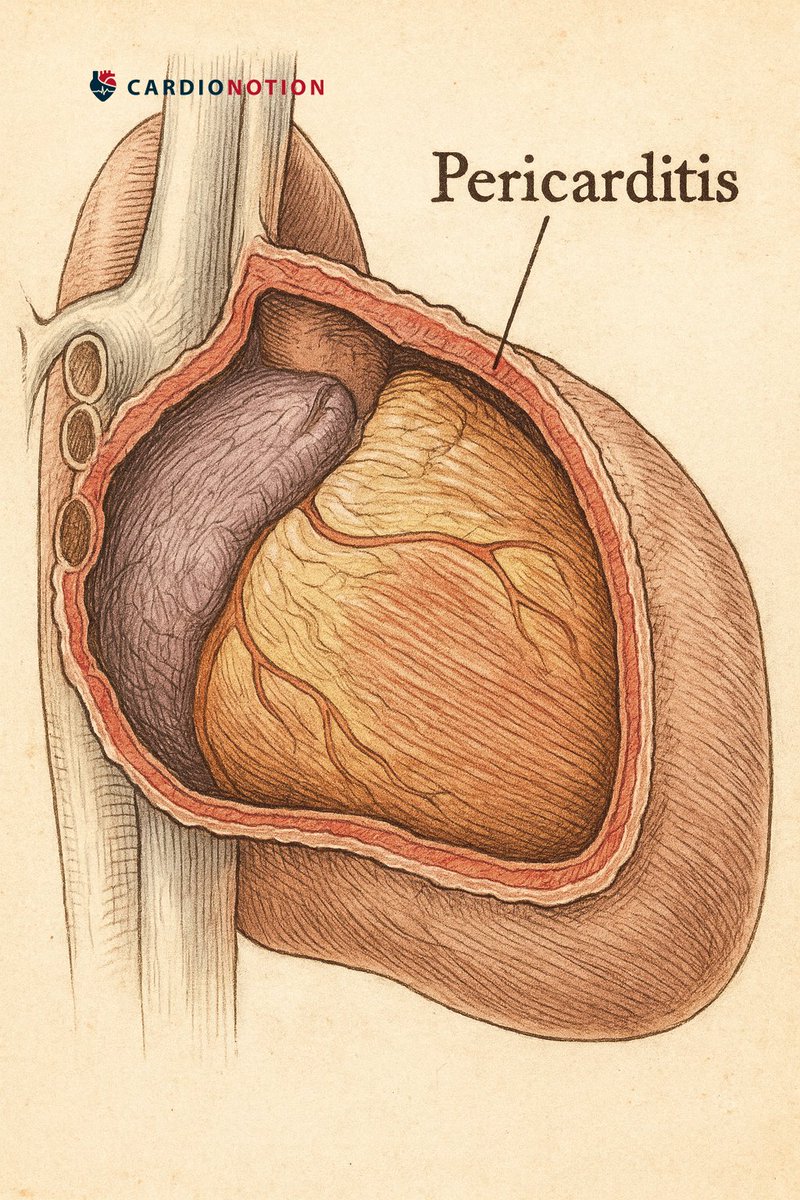

🚨Recientemente, las guías americanas de consenso han propuesto nuevos criterios para diagnosticar la #PERICARDITIS Te lo contamos en este hilo 🧵 👇🏻 #CardioEd #POCUS #CardioNotion